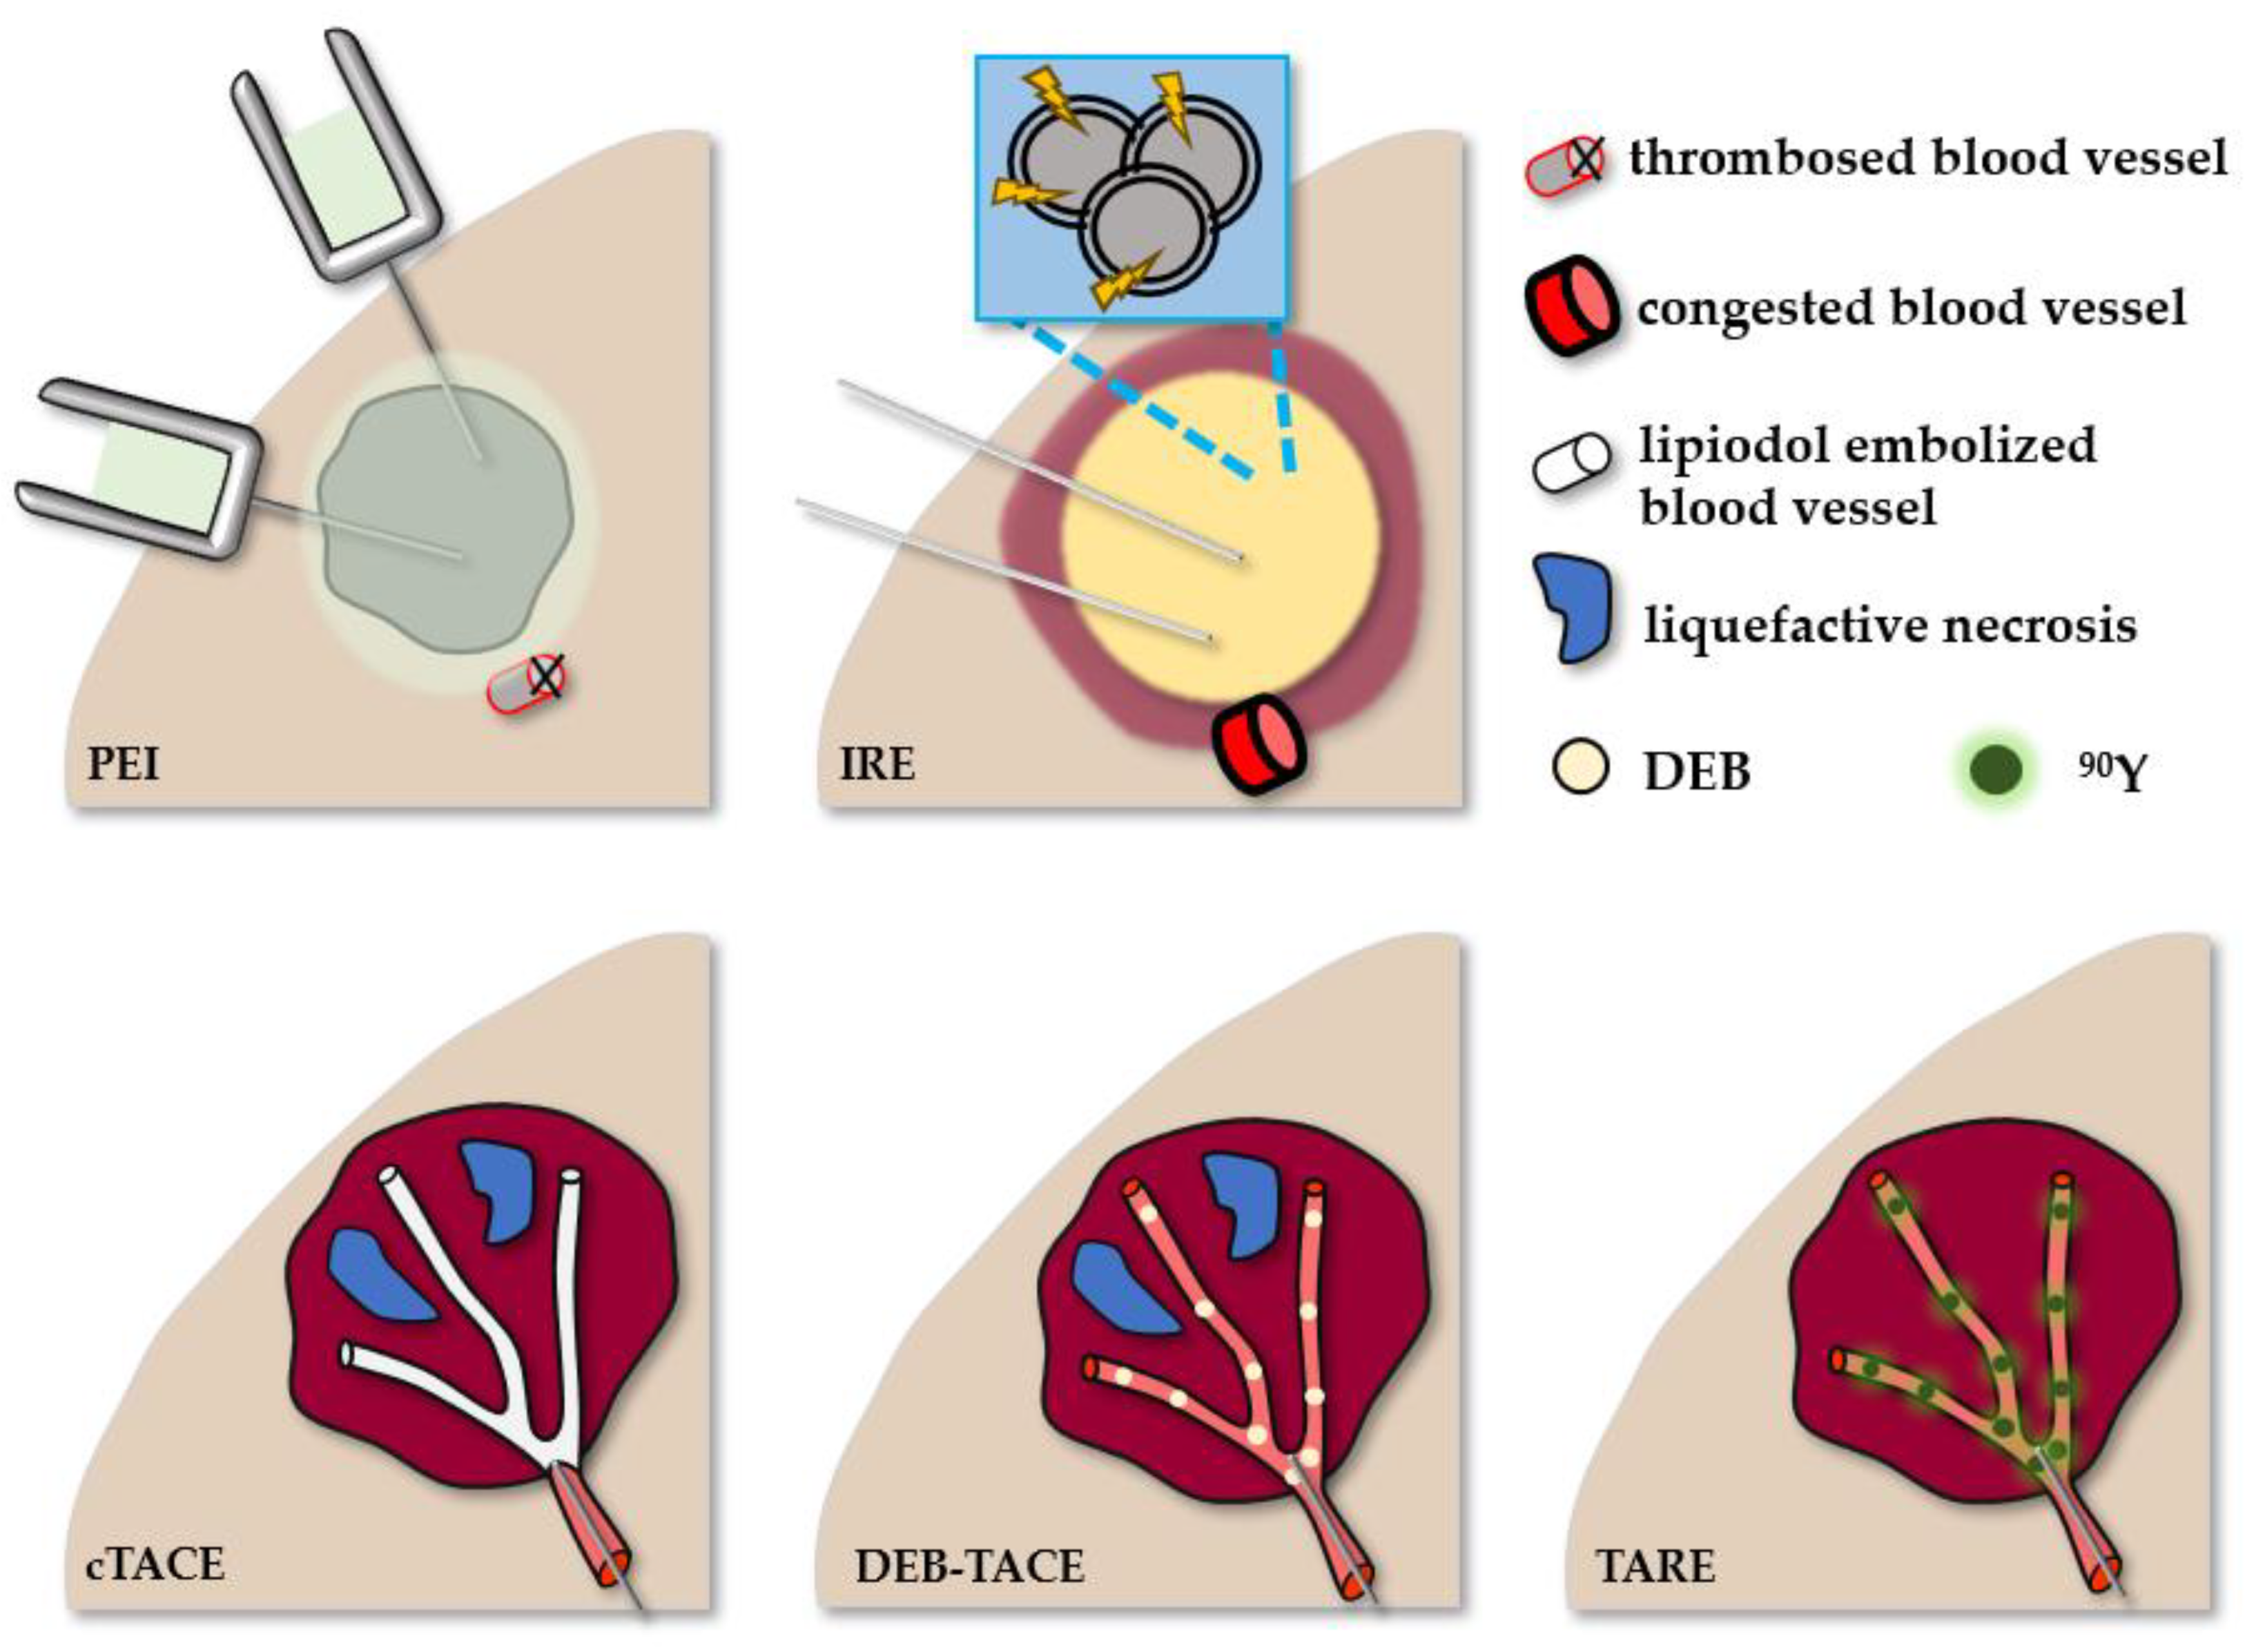

2. Minimally Invasive Therapies for HCC and Their Tissular Effects

2.2. Non-Thermal Ablative Therapies

2.2.1. Percutaneous Ethanol Injection

2.2.2. Irreversible Electroporation

2.2.3. Transarterial Chemoembolization

2.2.4. Yttrium-90 Radioembolization